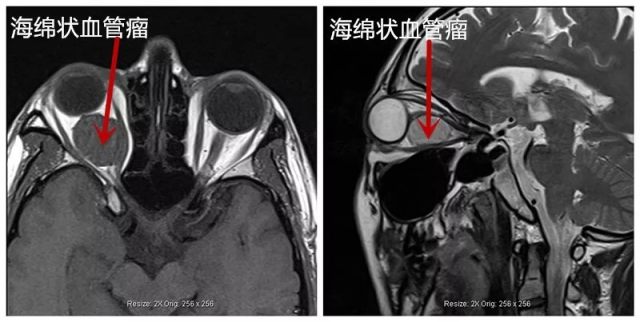

而医院这边,也因为李先生的病情紧急,特别为他开放绿色通道。 李先生下了飞机立即直驱医院,住院当天,就在各科室协调下顺利完成了所有术前检查。肖教授看了检查结果,亲切地安慰紧张焦虑的李先生和家人说:「放心吧,交给我!」手术第二天就在肖教授亲自操刀下顺利进行了,术后病理报告也证实与诊断一致:右眼眶海绵状血管瘤。

海绵状血管瘤是成年人最常见的原发于眼眶内的肿瘤(良性),病因尚不明确。最常见的临床体征是眼球突出,但这种缓慢的、渐进性的眼球突出,早期缺乏明显症状和其他体征,反而因为肿瘤压迫眼球导致眼轴缩短, 出现近视消失这一类的假错觉,让患者毫无察觉。 当肿瘤直径大于 10 mm 时, 才出现可见的眼球突出,此时,包块眼眶 CT、核磁检查均可发现眼底视网膜水肿,这是由于肿瘤直接压迫或影响局部血循环引起的,十分危险。